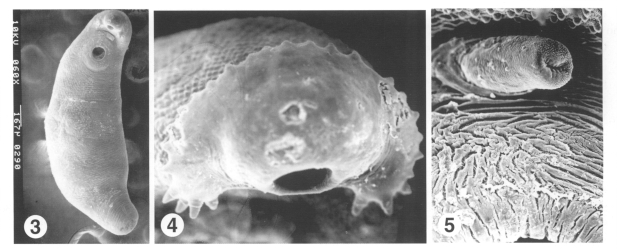

The flukes were processed for parasitological identification by light and scanning electron microscopic studies. The anterior of the fluke was bent ventrally at the acetabulum, and the surface was wrinkled transversely over the whole body. The body surface was covered with cobblestone-like cytoplasmic processes. Tegumental spines, scale-shaped with a broad base, were densely packed on the anterior surface of the body and then reduced in density and size on moving posteriorly (Fig. 3). The anterior end bulged into a head crown around the oral sucker. The head crown was armed with uninterrupted 27 collar spines, of which the 4 end-group spines were present at the both ends of the the head crown (Fig. 4). The outer surface of oral sucker was smooth and encircled with ciliated sensory (Type I) papillae arranged in 2-3 rows. Unciliated sensory (Type II) papillae, dome-like round structures, appeared on posterior half of the oral sucker lip. The acetabulum, wide-open, was aspinous with velvety cytoplasmic processes, and surrounded with Type I papillae. The cirrus erected from the genital opening revealed a velvety tegumental surface, and dense Type I sensory papillae, as compared with other parts of the body surface (Fig. 5).

The number of collar and end-group spines is species-identifying morphological characteristic of echinostomatid flukes. The echinostomes retrieved from the present patient under scanning electron microscopy revealed 27 and 4 spines, which is a species-characteristic of E. hortense. Surface ultrastructures, such as the arrangement of Type I sensory papillae on the oral sucker and around the acetabulum, and scale-shaped tegumental spines distributed at decreasing density posteriorly are consistent with previous descriptions of E. hortense (Lee et al., 1986b). After referring to surface ultrastructural characteristics and egg morphology (Seo et al., 1983), the isolated flukes were identified as E. hortense.